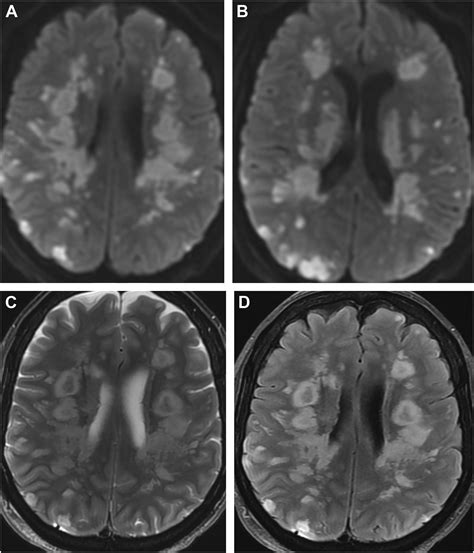

Diagnosing White Matter Disease typically relies on advanced imaging techniques rather than just clinical observation. Physicians look for specific patterns of damage that distinguish this condition from others like Alzheimer’s or stroke.

MRI (Magnetic Resonance Imaging) The gold standard for identifying white matter hyperintensities (bright spots on the scan indicating damage).